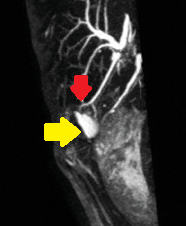

Yellow arrow — Contrast collection in the gallbladder fossa. Red arrow — Injured Luschka duct (Courtesy Dr. V. Penopoulos)

Patient CT, 6th postoperative day. Contrast in the gallbladder fossa. Red arrow — Injured Luschka duct (Courtesy Dr. V. Penopoulos)